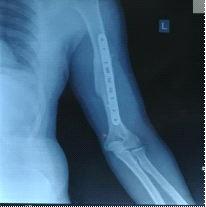

At the start of our study 22 patients had grade 1 and 2 nodularity and 30 patients had grade 3 and 4 nodularity At the end of the first month, there was no palpable nodularity in 17 patients, grade 1 and 2 nodularity in 17 patients and grade 3 and 4 nodularity in 18 patients. At the end of the second month, there was no palpable nodularity in 18 patients, grade 1 and 2 nodularity in 17 patients and grade 3 and 4 nodularity in 17 patients. At the end of the third month, there was no palpable nodularity in 38 patients, grade 1 and 2 nodularity in 13 patients and grade 3 and 4 nodularity in 1 patient. At the end of the sixth month, there was no palpable nodularity in 39 patients, grade 1 and 2 nodularity in 12 patients and grade 3 and 4 nodularity in only 1 patient. These findings have been illustrated in Figs 1-5.

Fig 1 — At the beginning of treatment

Fig 5 — At the end of sixth month

Fig 4 — At the end of third month

Fig 2 — At the end of first month

Fig 3 — At the end of second month